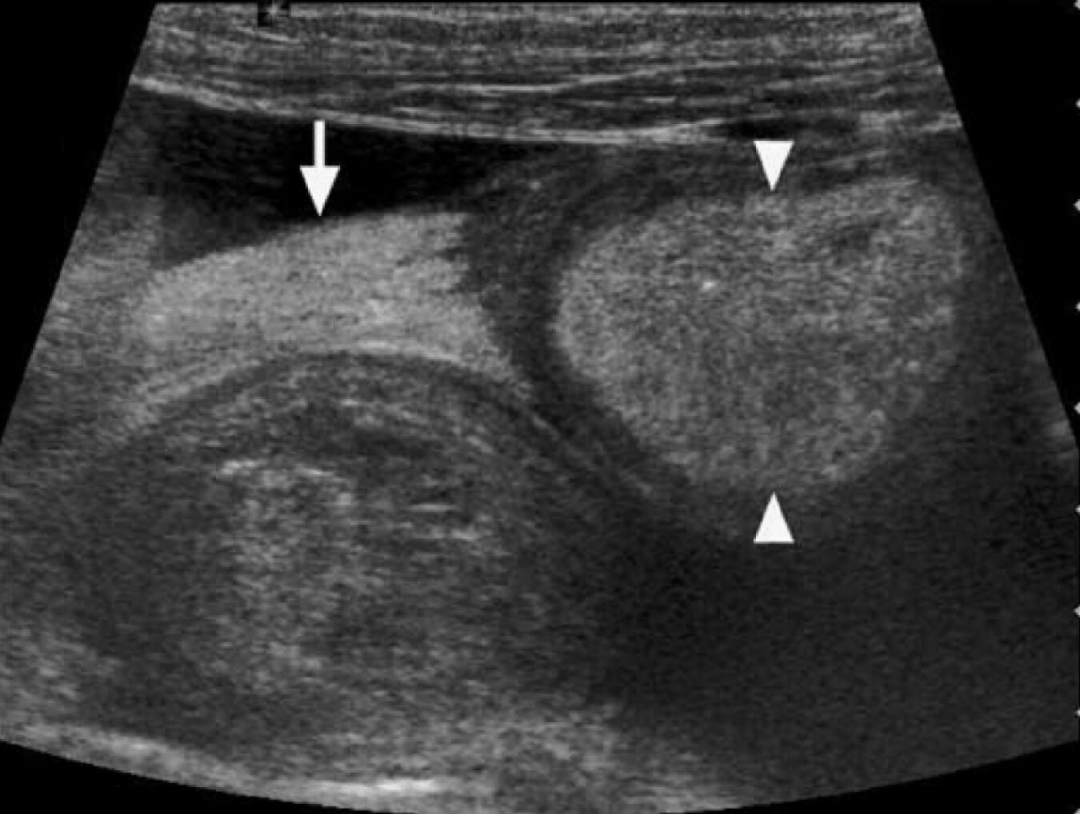

图4-6:Whipple病的“白肠、白淋巴结”。病例2,患者,男性,54岁,反复腹痛、腹泻、脂肪泻、关节痛。超声显示空肠段肠壁全层几乎呈弥漫性高回声(箭头所示),仅外层肌层呈薄层低回声带。同时,在肠系膜血管旁可见明显增大的高回声淋巴结(△所示),直径约20mm。该病例后经十二指肠活检确诊为Whipple病。Hint:这种“高回声肠壁-高回声淋巴结”的组合被认为是Whipple病的相对特征表现,而与之相应,Whipple病的病理特征即为肠黏膜及淋巴结内大量泡沫状巨噬细胞(含PAS阳性物质)浸润,这是产生高回声的基础之一。

图7:“白肠”和肠系膜静脉血栓。病例3,患者,男性,31岁,AIDS合并鸟胞内分枝杆菌感染,临床表现为体重下降、腹泻和低热。声像图一侧可见多个融合的低回声肿大淋巴结,而另一侧(箭头所指处)可见“白肠”。CDFI显示融合的肿大淋巴结旁存在迂曲扩张的静脉侧支循环,这是肠系膜静脉血栓形成的间接征象之一。该病例后经淋巴结穿刺确诊同时存在感染和血栓。Hint:淋巴系统病变(分枝杆菌感染所致淋巴结肿大)与静脉系统(静脉血栓形成)之间存在千丝万缕的联系。